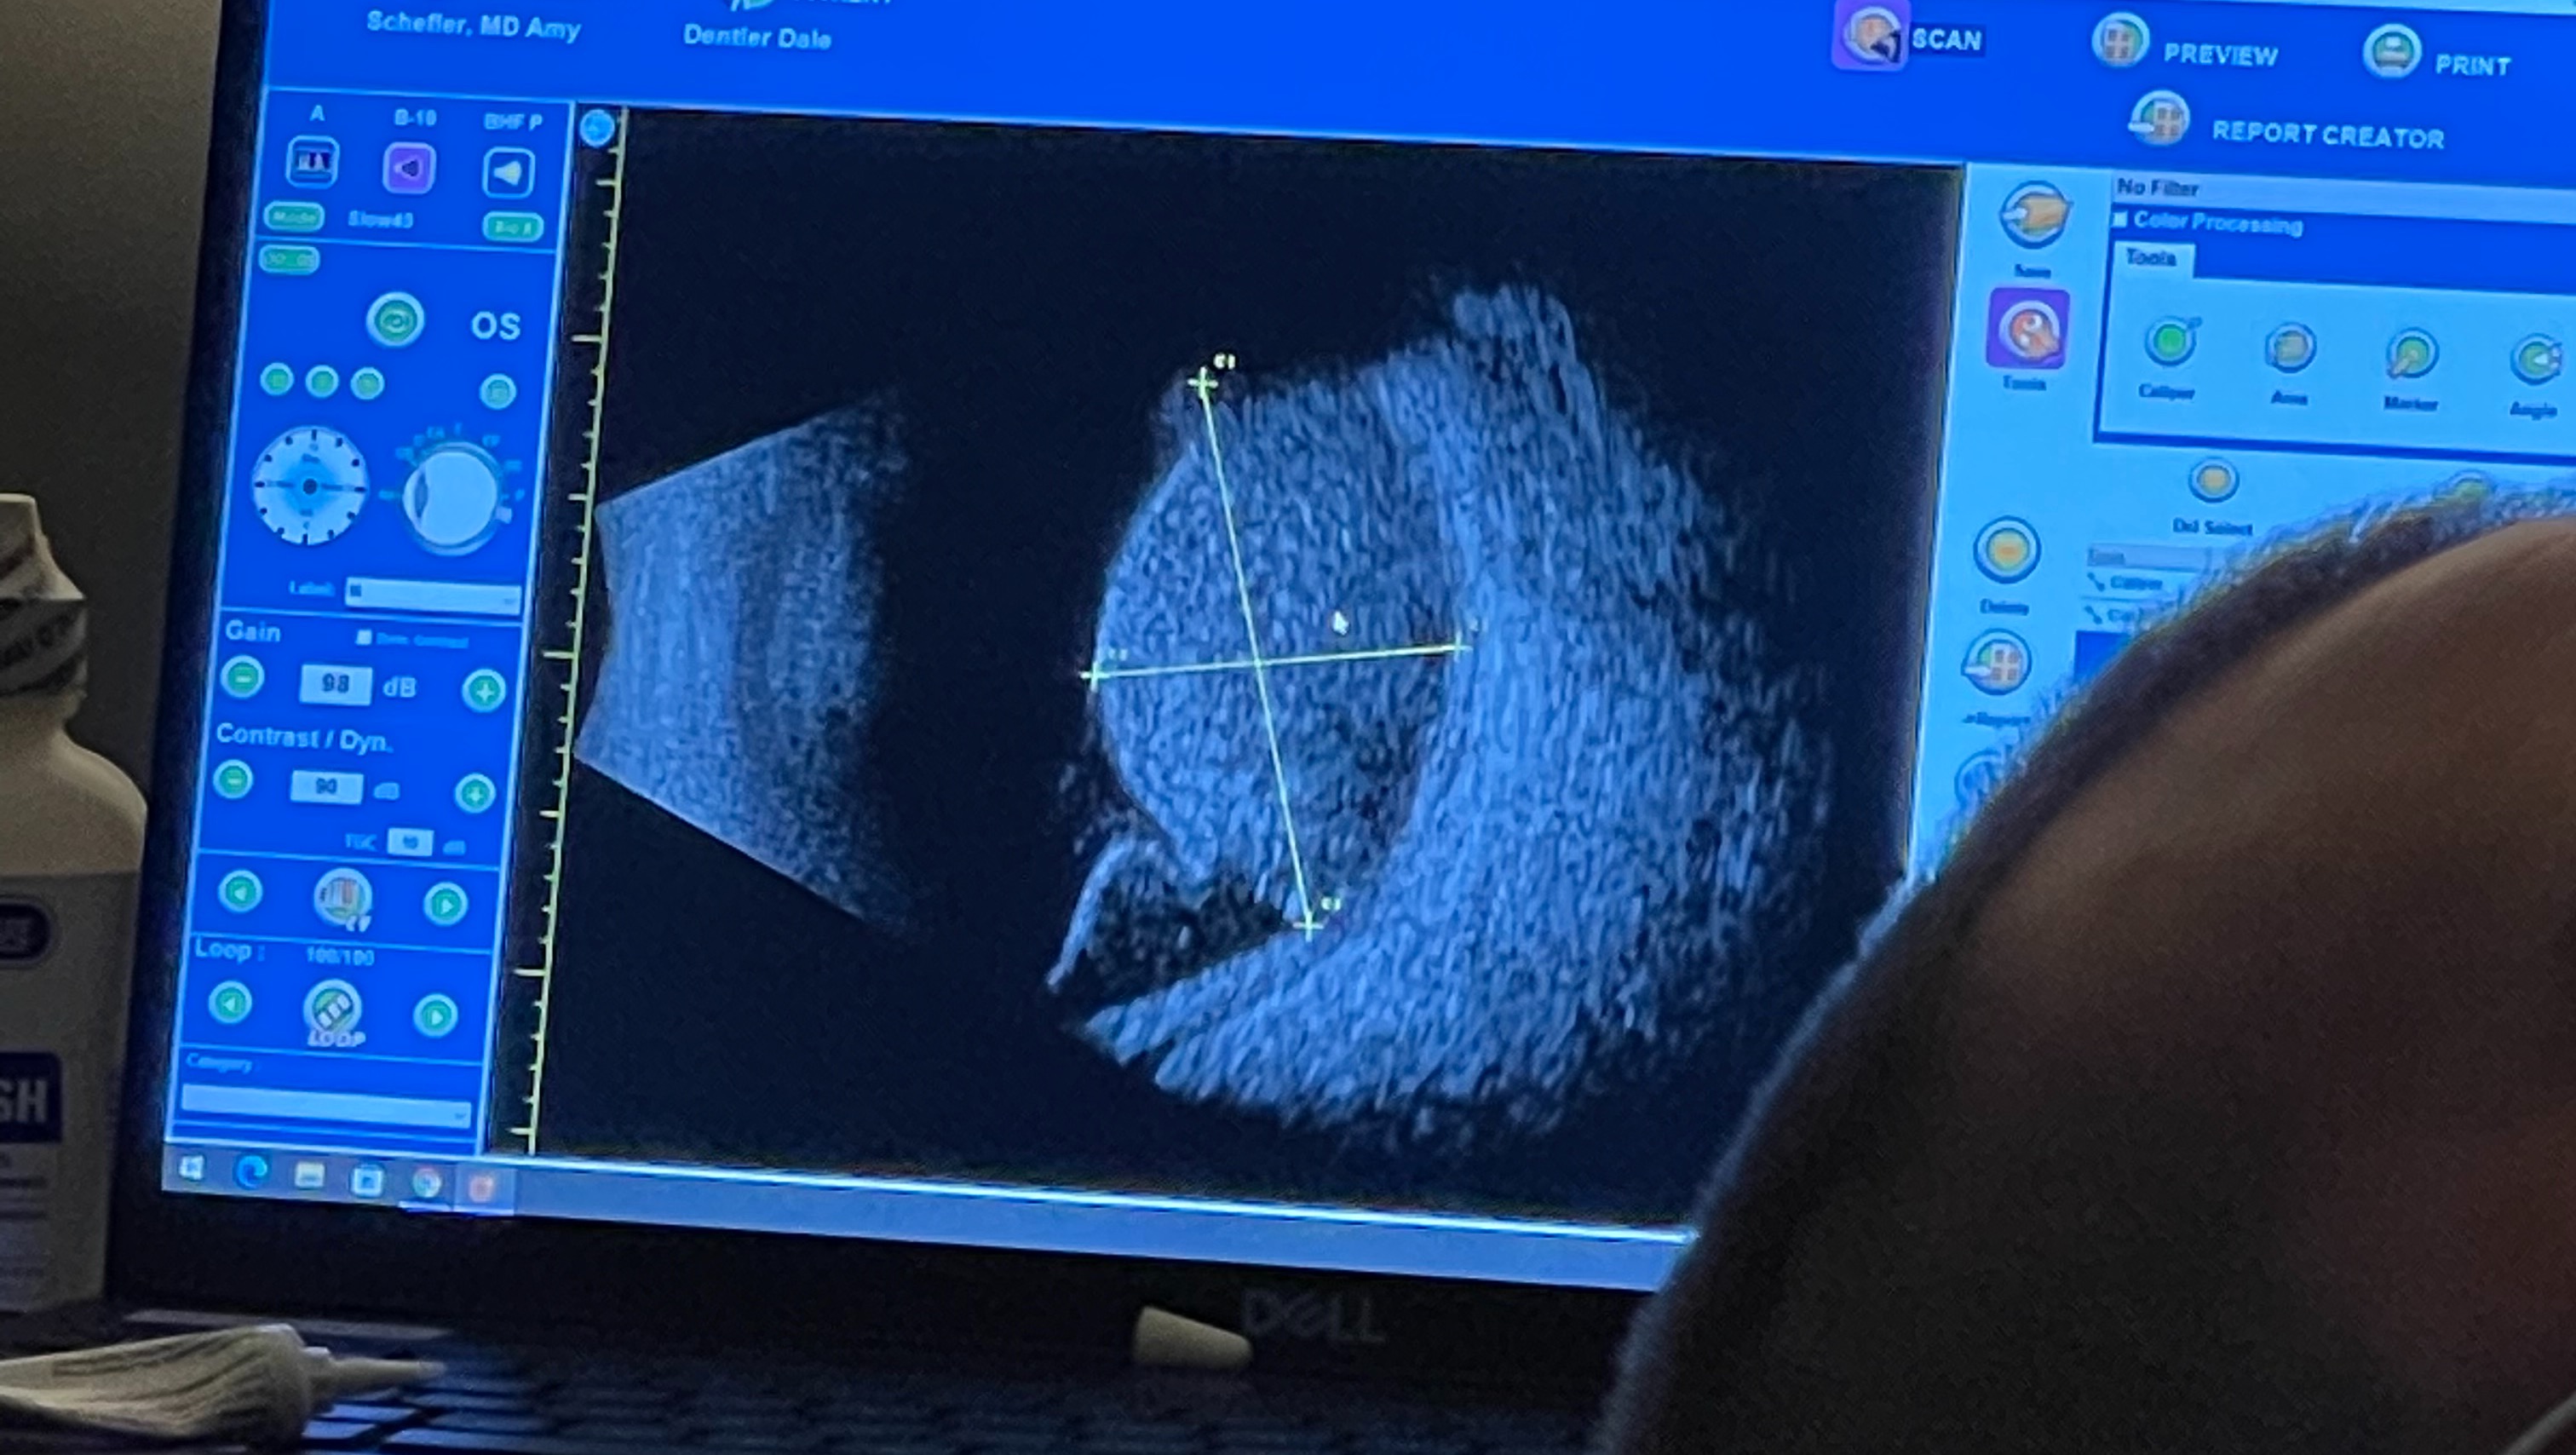

This is the latest image of his tumor on 11/30/21. Where you see the "cross hairs" it should be all black. A normal eye would not have any white areas where the yellow lines are. Dale's tumor is extremely large.

Dale's tumor measured 17.5 mm x 19 mm x 11.5 mm in his right eye on 11/30/2021. He has been experiencing severe vision loss which prompted him to see an eye specialist in Dallas, TX and that is when they found the tumor.

He's scheduled for surgery to insert his plaque for radiation on 1/3/22. This will administer radiation directly into his tumor and eye for 7 days in hopes it will kill the tumor. Dale's tumor is extremely large and Dr Schefler is anticipating that she will be able to save his eye from enucleation (eye removal) but she isn't 100% sure until Dale meets with the radiation oncologist that is on her team. So there is a possibility that he could lose his eye. Dr Schefler did go ahead and let Dale know that his vision is as good as its going to get right now. He can't really see anything right now because of the damage that the tumor is causing so quickly.

Dr Schefler is concerned that there may be a spot on the back of his tumor where it is trying to leave the eye and spread to the soft tissue. If this is happening, this is not good. She will not know until 1/3/2022 when she has him in surgery if this is happening or not.